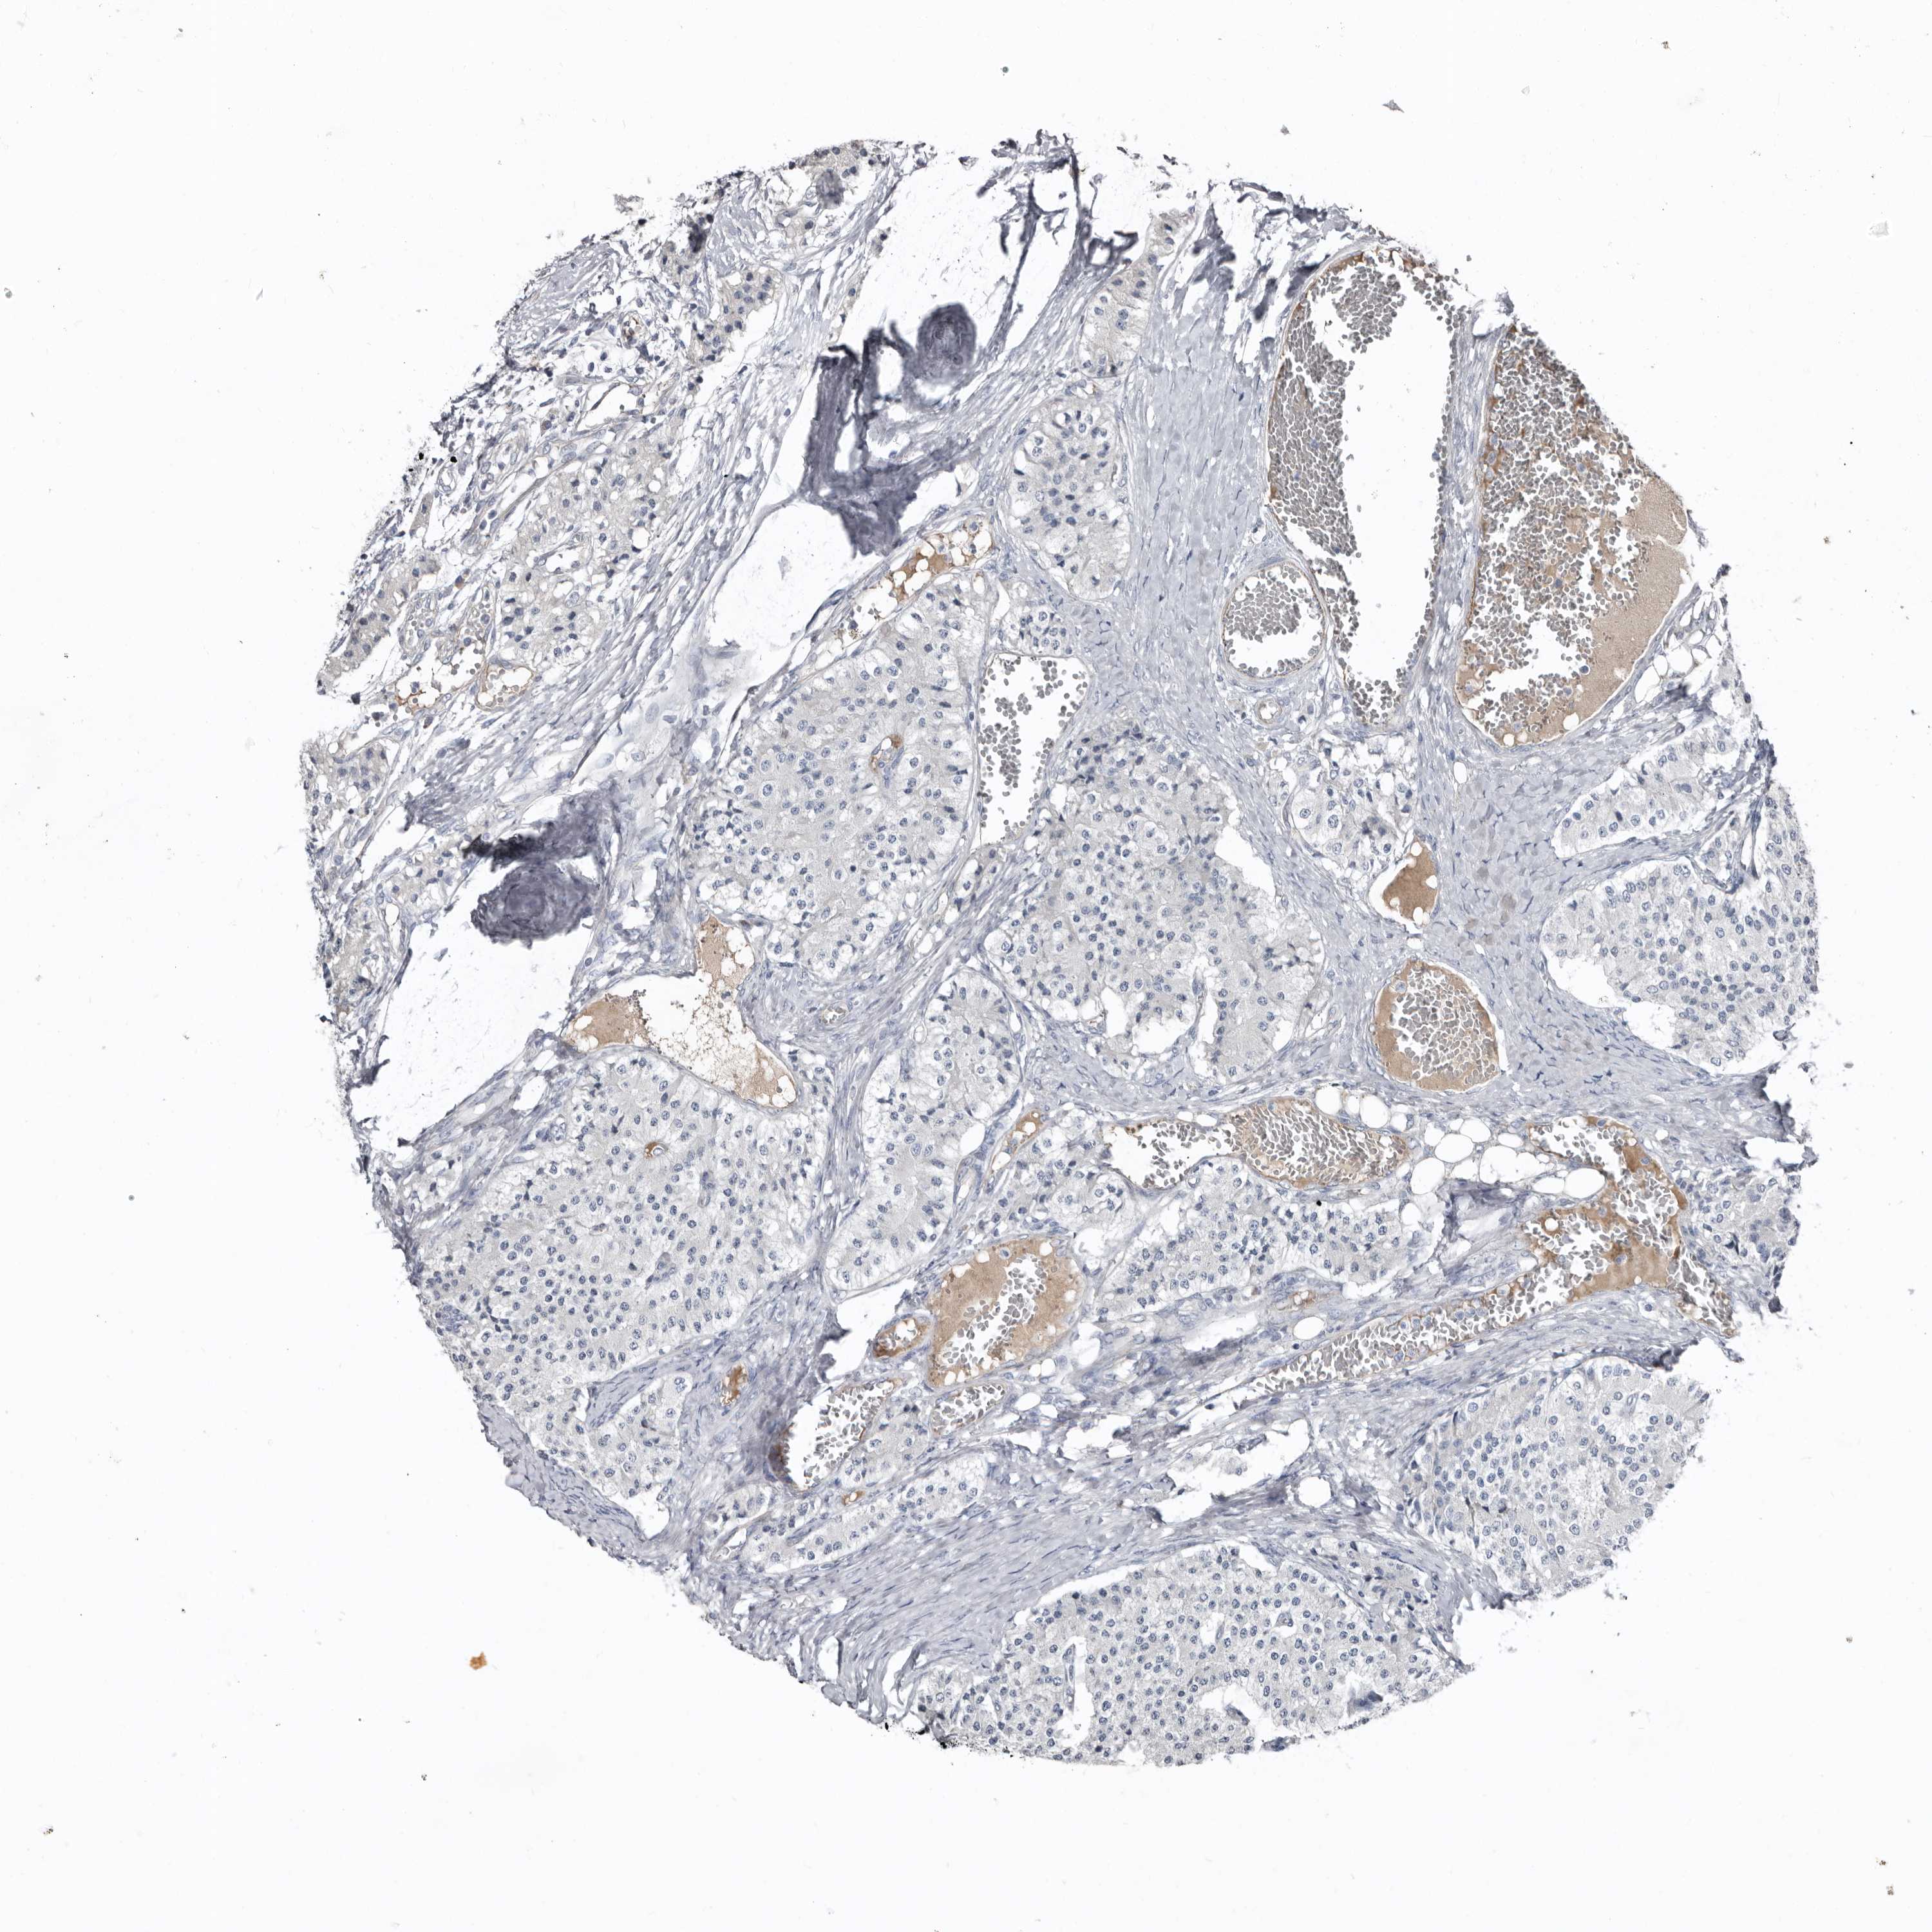

CARCINOID - Protein expressioni

A mouse-over function shows sample information and annotation data. Click on an image to view it in a full screen mode. Samples can be filtered based on level of antibody staining by selecting one or several of the following categories: high, medium, low and not detected. The assay and annotation is described here.

Antibody stainingi

Antibody staining in the annotated cell types in the current human tissue is reported as not detected, low, medium, or high, based on conventional immunohistochemistry profiling in selected tissues. This score is based on the combination of the staining intensity and fraction of stained cells.

Each image is clickable and will lead to virtual microscopy that enables deeper exploration of all samples and also displays staining intensity scores, fraction scores and subcellular localization as well as patient and tissue information for each sample.

Antibody HPA025019

Antibody HPA029553

Carcinoid, malignant, NOS

Carcinoma, NOS